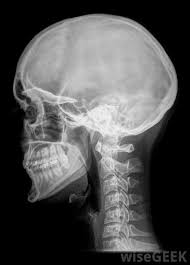

To check if bladder cancer has spread, ct scans may be used to create images of the entire urinary tract (including the kidneys) as well as lymph nodes, other organs in the abdomen, and the lungs. Symptoms of metastatic testicular cancer can include: As described (more briefly) in the hallmarks of cancer section, metastasis is responsible for the great majority of deaths in cancer patients.this section details the steps by which cancer cells spread around the body and form new growths. Now i know that is was'nt only the seeds b/c i have had 3 sessions of radioactive iodine too, but apricot seeds have the natural b17 vitamin that has been proved to fight cancer. Cancer may have spread to your lymph nodes. No matter where else in the body it spreads, a cancer is still named for the place it originated. Containing cancer when this type of cancer spreads (your doctor may say it has metastasized), it tends to first show up in the tissues or lymph nodes that are closest to the prostate gland. A handful of general symptoms can be signs your melanoma has spread, though they're pretty nonspecific—meaning they could be symptoms of many things, from the flu to cancer. Grade provides clues about how quickly the cancer is likely to grow and spread. Cancer which has spread to the lymph nodes can sometimes be detected if the lymph nodes have become enlarged. The most common symptom if cancer has spread to the bone is bone pain. How to know if cancer has spread. Your bones might also become weaker and more likely to break (fracture).

Stage iv means the cancer has spread to other organs. Sometimes cancer that starts in one part of your body, known as the primary site, spreads to other parts. Nearly 40% of those newly diagnosed with lung cancer are already at stage 4 and have metastases, cancer that has spread to other parts of the body. I also suffer back pain which i have had for months, although i am now aware it can be a sign that it has spread to my lymp nodes. If cancer cells have spread to your lymph nodes (or beyond your lymph nodes to another part of the body), symptoms may include: Cervical cancer may spread to the bones. Grade provides clues about how quickly the cancer is likely to grow and spread. Symptoms of metastatic testicular cancer can include: A handful of general symptoms can be signs your melanoma has spread, though they're pretty nonspecific—meaning they could be symptoms of many things, from the flu to cancer. No matter where else in the body it spreads, a cancer is still named for the place it originated. Your cancer can be stage 1, 2, 3, or 4. It is similar to a pet scan, but it uses a different radioactive substance that settles in areas of change in the bones. Metastatic cancer is a cancer that has spread from the part of the body where it started (the primary site) to other parts of the body.